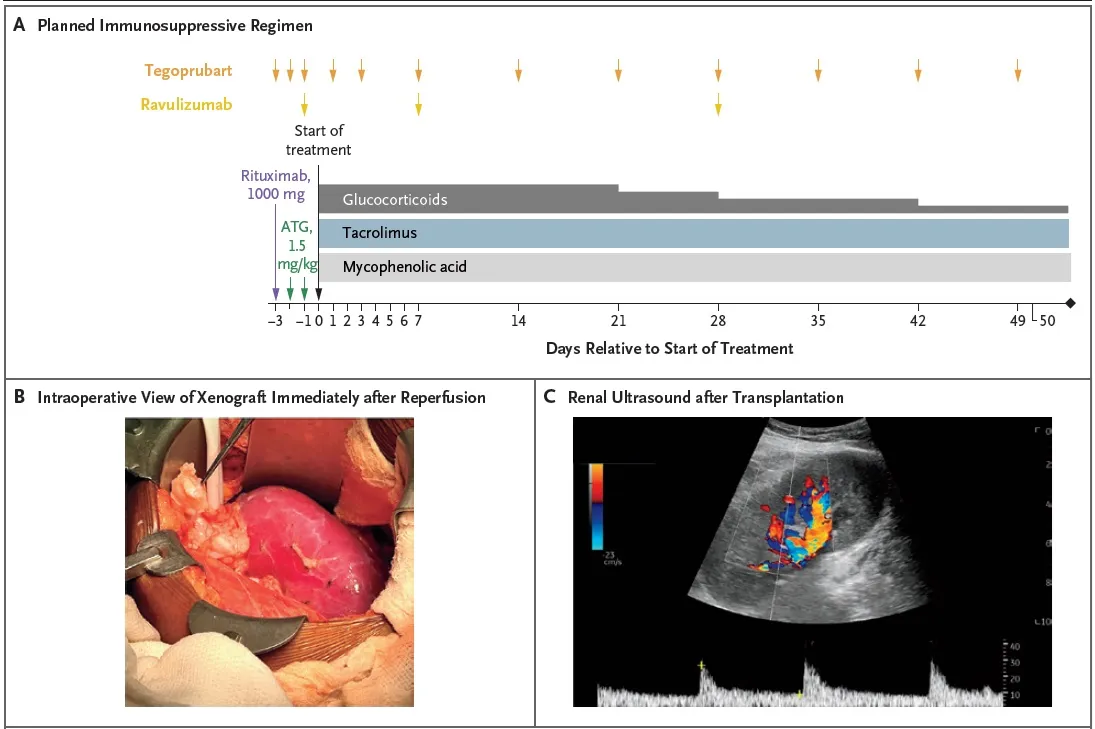

##### Imunossupressão utilizada

Indução

* Timoglobulina (ATG) 1,5 mg/kg

* Rituximabe (1000 mg)

* Tegoprubart (anti-CD154, bloqueia a produção de anticorpos)

* Ravalizumabe (anti-C5)

Manutenção

* Prednisona, tacrolimo e micofenolato

Tempo de isquemia fria: 4 horas e 38 minutos

Confere o esquema de imunossupressão utilizado, bem como achados do intraoperatório: